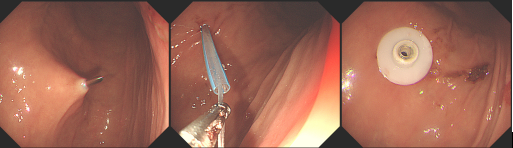

PEG是在内镜引导下,经皮穿刺放置胃造瘘管,营养液通过PEG喂养管直接输注到胃内,以达到胃肠道营养和其他治疗目的,PEG为建立长期的肠内营养通道提供了一种安全、有效途径。行PEG的前提是各种原因导致经口摄食障碍,但胃肠功能正常,需长期(2~3周以上)管饲营养支持或需长期胃肠减压者。